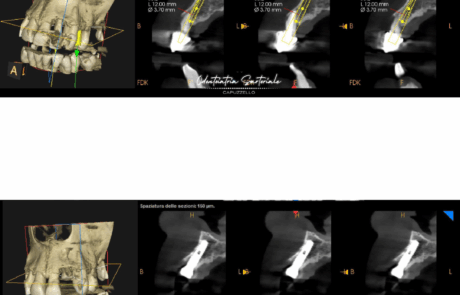

In questo caso abbiamo inserito un impianto post-estrattivo a carico immediato, guidati da una dima chirurgica digitale per lavorare al millimetro.

Le impronte mostrano il percorso:

👉 subito dopo l’estrazione

👉 appena posizionato l’impianto

👉 dopo 3 mesi, con tessuti perfettamente mantenuti